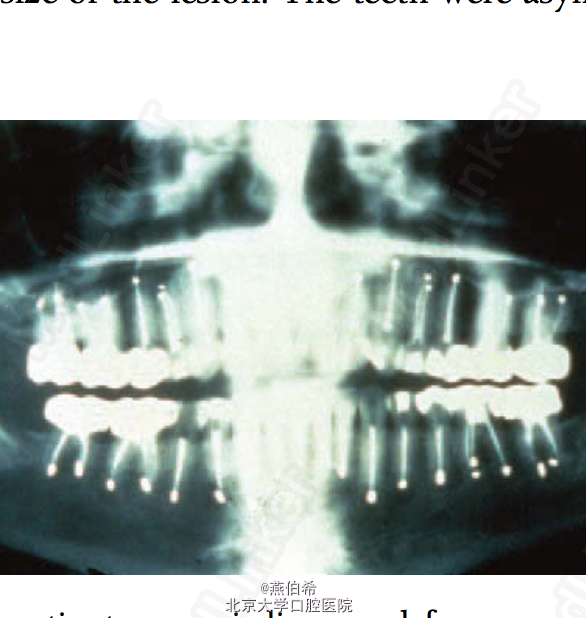

又一例错误判断为牙源性疼痛而导致的无用治疗。